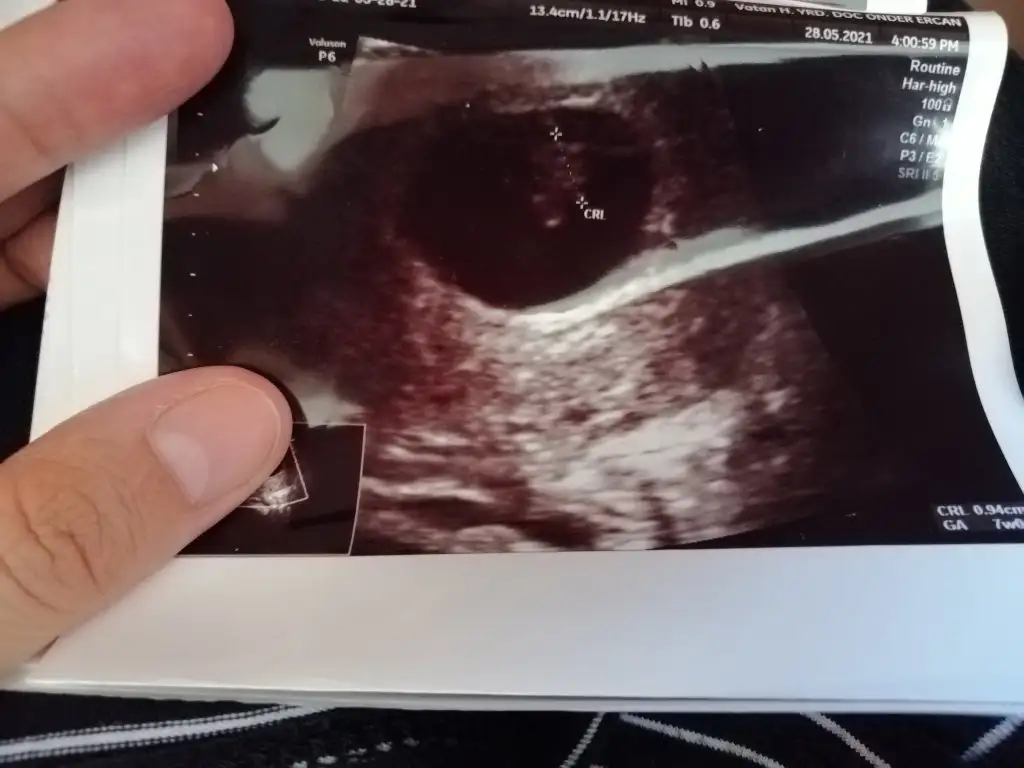

Selamlar herkese 😊 sabah doktora gittim baya büyümüş 🙈👶🏼 bes alti tup kan alindi hem kan testi hem ikili test icin bir de idrar tahlili istedi doktor. İnşallah güzel çıkacak sonuçlar 🙏

T tulperde rica etsem tahmin alabilir miyim cok arada kaldım 🙈 doktor bisey demedi

Pek tatlı biseye benziyor😍 sağlıcakla kucagina al ins